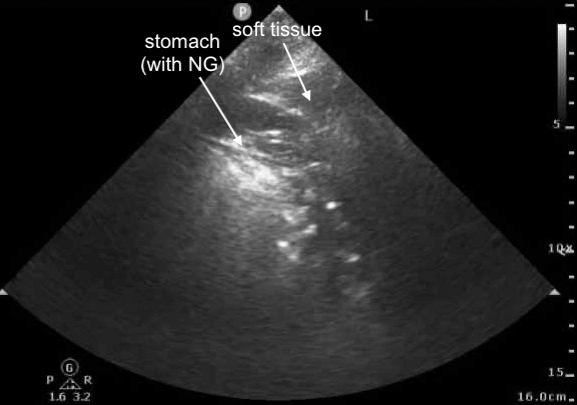

POCUS Image 3 - slightly more anterior - left mid-axillary line, probe marker cephalad, attempt to better understand structure above diaphragm

6/

With CT scan, we see that

-structure #1 is the stomach (with NG tube)

-structure #2 is soft tissue

12/